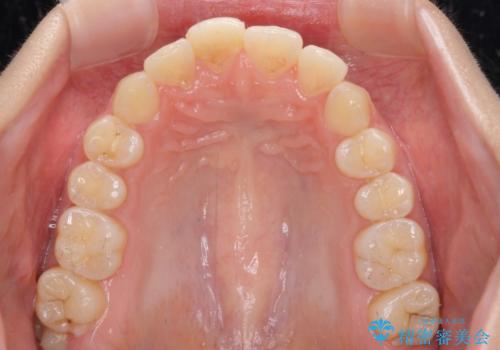

- 転んで前歯が欠けてしまったとのことで来院された患者様です。

転んで前歯の先端1/3ほどが欠けており、近医にて応急処置としてコンポジットレジン修復がされていました。

審美性や舌触り、今後の歯への負担などを考え、オールセラミッククラウンにて補綴治療を行うこととしました。